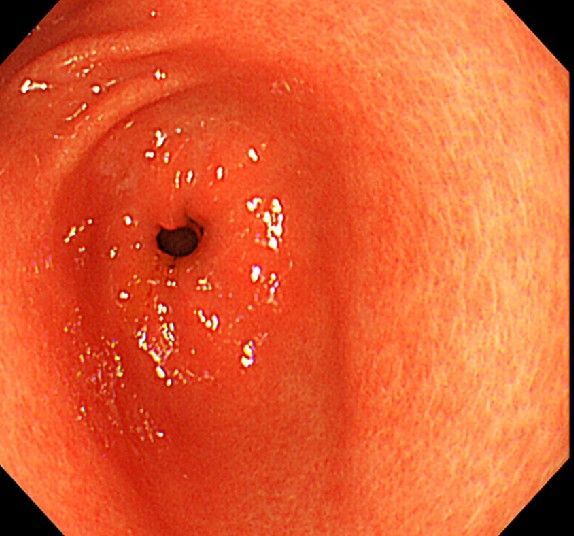

위 내시경을 찍었는데 위염 종류 사진을 알 수 있을까요? (사진 많습니다..)

한달 전 쯤에 소화불량과 속쓰림이 3개월 동안 약을 먹어도 낫지 않아 위 내시경을 찍었는데 위에 염증이 많이 있다는 이야기를 들었습니다...그런데 상태가 얼마나 안 좋은지 어떤 종류의 위염인지에 대해서는 물어봐도 안 알려주셔서 여기에라도 올려서 여쭈어봅니다... 제 상태가 얼마나 심각한 걸까요..

사진상으로 보아서는 정상에 가까운 점막상태이거나 약간의 표재성 위염이 있는 정도로 보입니다.

홍반성 위염이 있으며 경증의 역류성 식도염이 있습니다